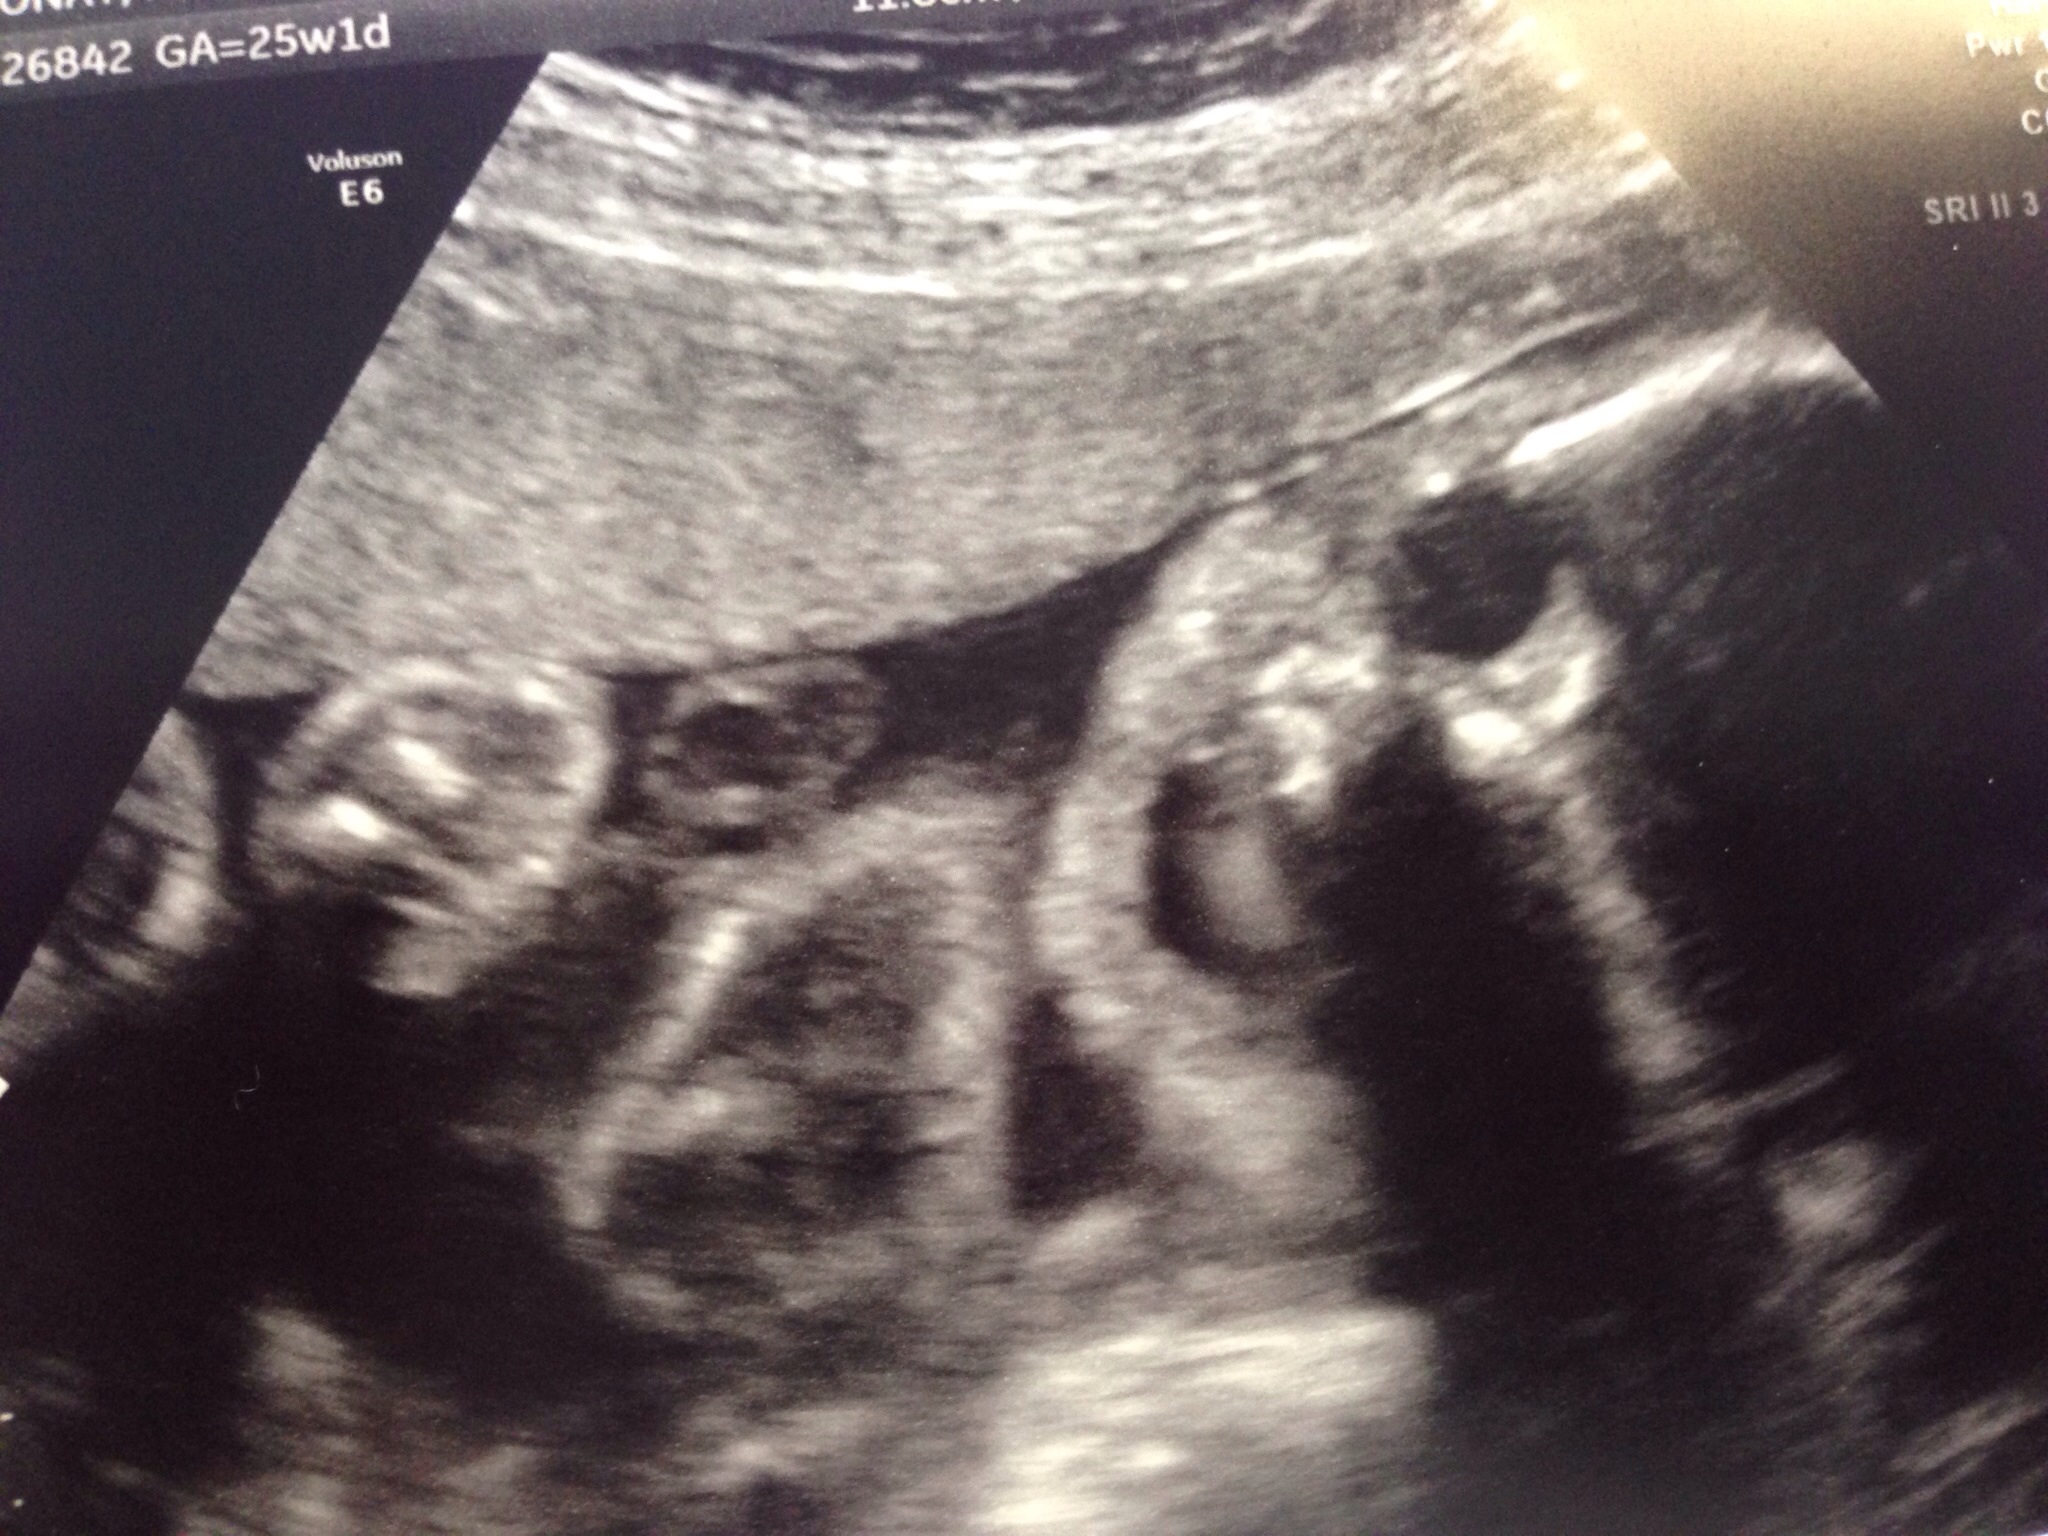

Had my 25 week check up and u/s due to my husbands heart defect and couldn't see the heart well enough last time. So far everything looks good but still can get good pics of the heart because baby is on his stomach. Oh well just means another u/s in a few weeks. Along with my glucose screen. Here's a pic of my little guy